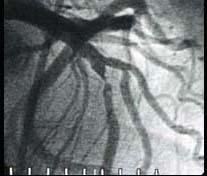

问题 图中冠状动脉造影结果为 ( )

选项 A、右冠近端95%狭窄 B、前降支近中端95%狭窄 C、右冠远端95%狭窄 D、左冠回旋支95%狭窄 E、左主干近端95%狭窄

答案 B